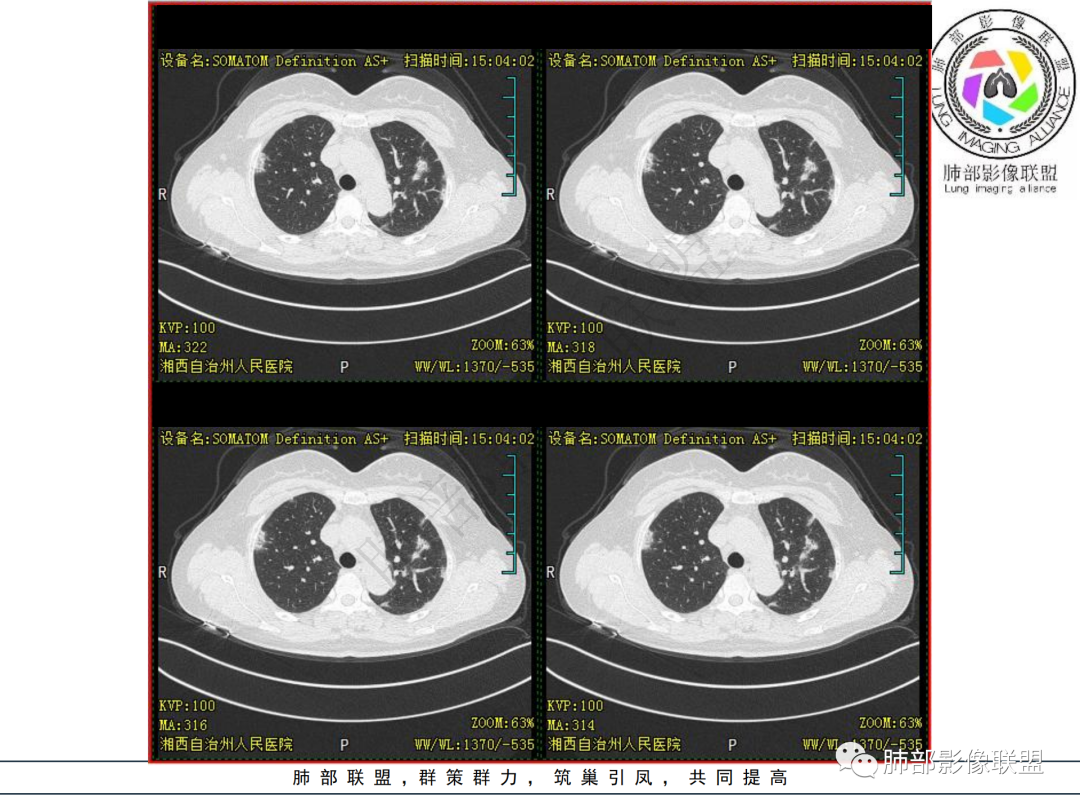

中年妇女,类风湿性关节炎病史,RF升高,感染性指标正常,双肺散在多发结节、斑片、条片灶,边缘欠清晰,大部分胸膜下分布,部分反晕,考虑RA-ⅠLD ,OP样改变

中年女性,有类风湿关节炎病史,双肺内及胸膜下见多发结节,条索状及小实变影,部分结节病灶垂直支气管血管束生长,部分结节病灶内见偏心性空洞形成,病灶收缩力弱,病灶形态多样,部分可见纤维化样改变,整体符合Op表现,结合患者病史,考虑类风湿结节,隐球菌感染不能排除。

中年女性,类风湿关节炎病史,双肺散在结节影,胸膜下分布为主,部分可见小空洞影,部分可见索条影,OP样改变,考虑类风湿结节,鉴别隐球菌

双肺散在多发结节及斑片,边缘欠清晰,胸膜下分布为主,部分内可见支气管扩张,妇女,类风湿性关节炎病史,RF升高,感染性指标正常,考虑RA-ILD,鉴别淋巴瘤。

女性,49岁,多关节肿痛一年余,类风湿因子升高。CT示双肺多发斑片影结节影,胸膜下为主,部分内部可见支气管扩张,部分内部似见小空洞影,复查CT进展,首先考虑为RA—ILD,鉴别CTD—ILD

双肺多发结节状及斑片状不均质磨玻璃病灶,胸膜下分布为主,边缘有收缩、凹陷,部分反晕,病灶内可见支气管扩张。中年女性,类风湿关节炎,感染指标正常。类风湿结节?隐球菌?

女,49岁,类风湿因子升高,影像双肺斑片及小结节影,胸膜下分布为主,部分病灶内支气管扩张,双侧胸膜增厚,复查病灶增多增大,考虑RA_ILD。

女性,49岁,多关节肿痛1年余。RF升高。胸部CT:双肺多发斑片影、结节影,胸膜下为主,部分沿支气管血管束分布,大小不等,部分病灶内支气管扩张,部分呈反晕,部分呈楔形宽基底贴附胸膜,复查CT进展,考虑:CTD—ILD?OP?鉴别血管炎、HP、肺梗、曲霉等。

中年女性,多关节肿痛一年,类风湿因子增高,双肺及胸膜下可见多发大小不一结节,部分呈楔形,以胸膜下分布为主,边缘平直,部分病灶分布于支气管血管束,部分可见空气支气管征、反晕征,复查病灶进展,类风湿结节?OP?

中年女性,类风湿病史,无发热咳嗽,炎性指标不高,类风湿指标高。影像 :双肺多发结片状、结节状稍高密度影,双肺外周分布为主,延支气管血管束分布,大部分病灶边缘平直,部分病灶内网状改变,有病灶跨叶,支气管血管束增粗,肺动脉高压,考虑类风湿结节,机化性肺炎,鉴别肉芽肿性血管炎,

双肺多发结节,胸膜下为主,内见空洞,边缘模糊见毛刺。类似病灶可见于:肺结核、肺隐球菌病、SPE、血管炎、类风湿结节……无发热、白细胞计数不高,排除SPE;无发热、消瘦、盗汗等症状,病灶形态较单一、无树芽征,肺结核可能性小;无多系统损害,GPA可能性小;肺内病灶较多,无明显临床症状,隐球菌抗原阴性,肺隐球菌病可能性小。结合病史,考虑类风湿结节可能性大。鉴别隐球菌病、肺结核。

2.双肺多发片状影,胸膜下分布为主,部分沿支气管血管束分布,边界不清,实性及磨玻璃密度,趋于柔和,可见支气管进入或穿行,未见空洞、钙化及树芽等。部分病灶显示反晕。